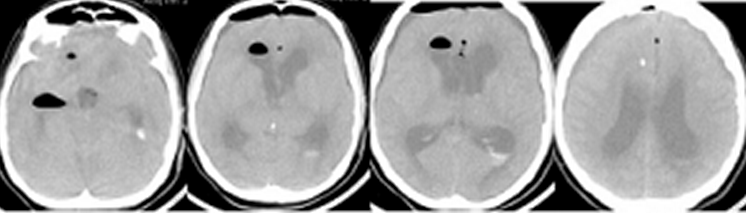

Пациентка Ч, 41 года, поступила в Институт с диагнозом: множественные аневризмы сосудов головного мозга – гигантская эксцентричная фузиформная аневризма области бифуркации левой ВСА с распространением на М1 сегмент левой СМА и аневризма небольших размеров развилки правой ВСА, рецидивирующие субарахноидальные кровоизлияния (САК), подострая внутримозговая гематома области Сильвиевой щели слева. Пациентка дважды переносила САК из аневризмы левой ВСА: за 1,5 месяца и 7 суток до госпитализации в Институт. При поступлении больная предъявляла жалобы на умеренную головную боль, очаговой неврологической симптоматики не выявлялось, по шкале Ханта-Хесса тяжесть состояния оценивалась в 1 балл. Ввиду гигантского размера и фузиформного характера аневризмы операция была технически сложной: проводилось многократное временное клипирование (по 5-7 мин) задней соединительной артерии, левой передней мозговой артерии, общей и наружной сонной артерии на шее, многократное репозиционирование клипсов на шейке аневризмы, внутрисосудистая аспирация крови из левой внутренней сонной артерии. По данным допплерографии наблюдалось преходящее снижение кровотока в дистальных отделах М1 сегмента левой СМА, что потребовало дополнительного пережатия общей и наружной сонной артерии на шее в течение 9 мин. Была также удалена гематома левой височной доли. Через 1,5 часа после завершения операции на фоне пробуждения из наркозного сна и появления реакции на интубационную трубку выявлялся правосторонний гемипарез, инструкций пациентка не выполняла. В контексте особенностей проведенной операции состояние было расценено как формирующееся ишемическое повреждение мозга, и было принято решение о незамедлительном начале ИГ для защиты головного мозга. ИГ проводилась в соответствии с описанным выше протоколом. КТ головного мозга выявило послеоперационные изменения (Рисунок 1).

Через 1,5 часа после завершения операции на фоне пробуждения из наркозного сна и появления реакции на интубационную трубку выявлялся правосторонний гемипарез, инструкций пациентка не выполняла. Состояние было расценено, как формирующееся ишемическое повреждение мозга, и было принято решение о незамедлительном начале ИГ для защиты головного мозга. ИГ проводилась в соответствии с описанным выше протоколом. Гипотермия была достигнута в течение 3,5 часов. Гемодинамика была стабильной. Проводилось энтеральное питание. Лабораторные показатели были в пределах нормы. Гипотермия продолжалась в течение 2 суток, после чего было начато согревание. Седация была прекращена при достижении нормотермии. Неврологический дефицит отчетливо регрессировал: восстановились сознание и движения в правых конечностях. При контрольном КТ-исследовании головного мозга очагов ишемии не выявлялось (Рисунок 1). Температура оставалась в пределах нормы, поэтому охлаждающий катетер был удален на следующий день. Осложнений ИГ не было. ИВЛ продолжалась еще в течение 4 суток. После экстубации пациентка наблюдалась в отделении реанимации еще 2 суток. Из Института больная выписана на 23 сутки после операции в удовлетворительном состоянии без очагового неврологического дефицита.